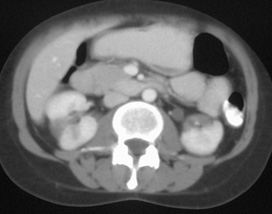

CT In Renal And Perirenal Lymphoma: A Further Look

CT IN RENAL AND PERIRENAL LYMPHOMA 235 (a) Fig. 4 Direct infiltration of the left kidney from a retroperitoneal mass in non-Hodgkin's lymphoma. ... Read Document